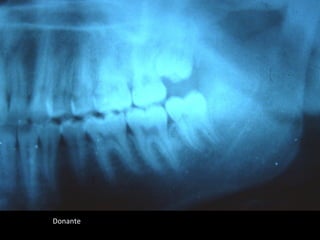

Donante